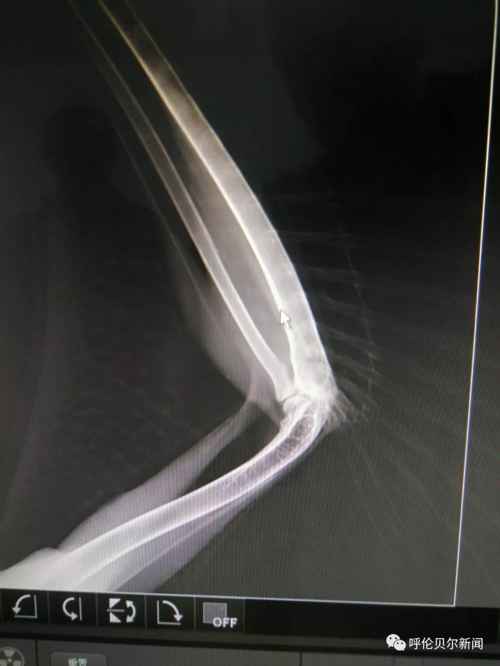

“我折了,希望有好心人能救助我!”2018年8月25日中午13:54分,双龙发了第一条关于这只雕鸮的微信朋友圈。“医院给雕鸮拍了x光片,发现右尺骨和桡骨两处骨折。身边没有能给宠物做手术的医生,我把图片发到朋友圈求助,咨询我市多名专家,他们都说桡骨非常细而且骨头很脆很难固定,手术难度太大。”双龙说。 “伤口感染,羽毛上的血渍结成了块,鸟的眼神里满是警惕和无奈,草原猛禽的风姿不再,可怜巴巴的样子,很让人心疼。”一直跟踪采访的新右旗融媒体中心记者巴图毕力格说。 >>>2018年8月31日 一边精心喂养,一边筹集为雕鸮治疗的资金,并通过微信群等方式寻找医生。经一名台湾野生保护志愿者联系,8月31日,双龙联系了毕业 于中国农业大学动物医学院、中国执业兽医师张拥军医生。 “我是一只国家二级保护动物雕鸮,我受了很重的伤,幸运的是我遇到双龙老师和张医生,他们没有放弃我……”一段雕鸮自述在腾讯公益被转载,很多野生动物保护志愿者解囊相助。5232.46元的爱心款向巴尔虎草原汇集。

在北京的张拥军医生看了X光片后表示可以进行手术,但是现在跨省运输国家二级野生保护动物审批手续繁琐时间太长,为了能够尽快手术,张拥军医生决定在海拉尔“出诊”。几经周折,双龙在海拉尔找到具备做手术条件的玩皮宠物医院,这家医院不仅同意免费提供手术场还表示愿意提供各种手术器具和药品。

>>>2018年9月3日 9月的草原日渐苍凉。清晨,双龙带着雕鸮行程300多公里来到海拉尔。一场秋雨让海拉尔这座城市清新怡人。玩皮宠物医院手术室内,来自北京的张拥军医生为雕鸮做了手术,海区几家宠物医院的医师均前来做助理、观摩学习。“手术难度比较大,术后休养也很重要,我会尽全力完成的。”张拥军医生结合20多年的临床经验,为在场的技术人员讲解手术要领。手术期间,记者进入手术室,看到双龙一边给张医生做助手,一边用蒙语安抚雕鸮。